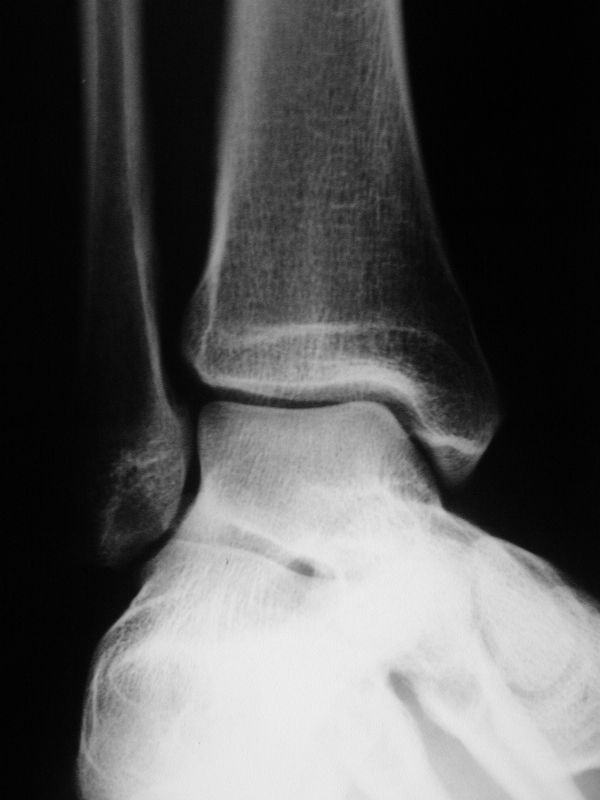

Röntgenaufnahmen dienen primär dem Ausschluss einer knöchernen Verletzung. Die Beurteilung der Geometrie der Malleolengabel kann einen ersten Hinweis auf eine Syndesmosenverletzung liefern. Die notwendigen Röntgenaufnahmen umfassen das Sprunggelenk anterior-posterior, lateral und in 20° Innenrotation (Mortise view). Zur Beurteilung der Syndesmose sind verschieden Parameter in der Mortise view beschrieben. Zu diesen zählen der tibiofibulare Clearspace, der mediale Clearspace, sowie die Überlappung der distalen Fibula und Tibia im Bereich der Incisura (Abbildung 2). Der Tibiofibulare Clearspace wird als verlässlichster Indikator für eine Syndesmosenverletzung gesehen, da er nicht signifikant von der tibialen Rotation beeinflusst wird 32. Er wird 1 cm proximal des Tibiaplafonds gemessen und sollte weniger als 6mm betragen 33. Jede Messung, die diesen Wert übersteigt, stellt einen Hinweis für eine Syndesmosenverletzung dar. Eine tibiofibulare Überlappung von 6 mm oder mehr in der AP Aufnahme, sowie mehr als 1 mm in der Mortise View Aufnahme gelten als physiologisch 33. Der mediale Clearspace sollte nicht mehr als 4 mm betragen 34.

Abbildung 3 zeigt ein Sprunggelenk nach Syndesmosenverletzung mit einem erweiterten Tibiofibularen Clearspace.